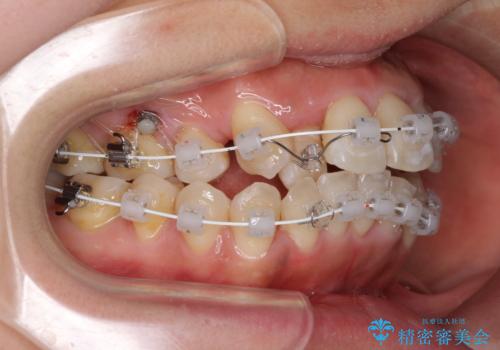

- 審美装置

上顎骨を急速拡大装置により拡大し、ワイヤー装置による抜歯矯正治療を行うこととしました。

治療途中、長期間海外旅行をされたり、帰国後には遠方へ転居されたりと、治療期間が伸びましたが、2年強で治療を終えることができました。